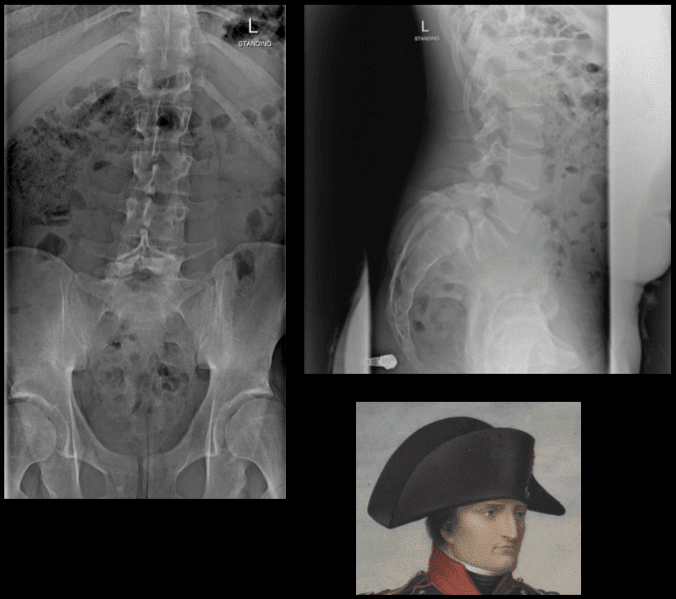

Studji dwar l-Immaġini

L-immaġini f'mard deġenerattiv tad-diska tintuża prinċipalment biex tiddeskrivi relazzjonijiet anatomiċi u karatteristiċi morfoloġiċi tad-diski affettwati, li għandha valur terapewtiku kbir fit-teħid ta 'deċiżjonijiet futuri għal għażliet ta' trattament. Kwalunkwe metodu ta 'immaġini, bħal radjografija sempliċi, CT, jew MRI, jista' jipprovdi informazzjoni utli. Madankollu, kawża sottostanti tista 'tinstab biss fi 15% tal-pazjenti billi l-ebda bidliet radjoloġiċi ċari ma huma viżibbli f'mard deġenerattiv tad-diska fin-nuqqas ta' ħernja tad-diska u defiċit newroloġiku. Barra minn hekk, m'hemm l-ebda korrelazzjoni bejn il-bidliet anatomiċi li dehru fuq l-immaġini u s-severità tas-sintomi, għalkemm hemm korrelazzjonijiet bejn in-numru ta 'osteofiti u s-severità ta' uġigħ fid-dahar. Bidliet deġenerattivi fir-radjografija jistgħu jidhru wkoll f'nies bla sintomi li jwasslu għal diffikultà biex jikkonformaw ir-rilevanza klinika u meta tibda l-kura. ("Marda tad-Diska Deġenerattiva" Fiżjopedja)

Ir-Radjografija

Din ir-radjografija ċervikali sempliċi rħisa u disponibbli b'mod wiesa 'tista' tagħti informazzjoni importanti dwar id-deformitajiet, l-allinjament, u bidliet deġenerattivi taż-żaqq. Sabiex tiġi ddeterminata l-preżenza ta 'instabilità ta' l-ispina u bilanċ sagittali, għandhom isiru studji ta 'flessjoni dinamika jew estensjoni.